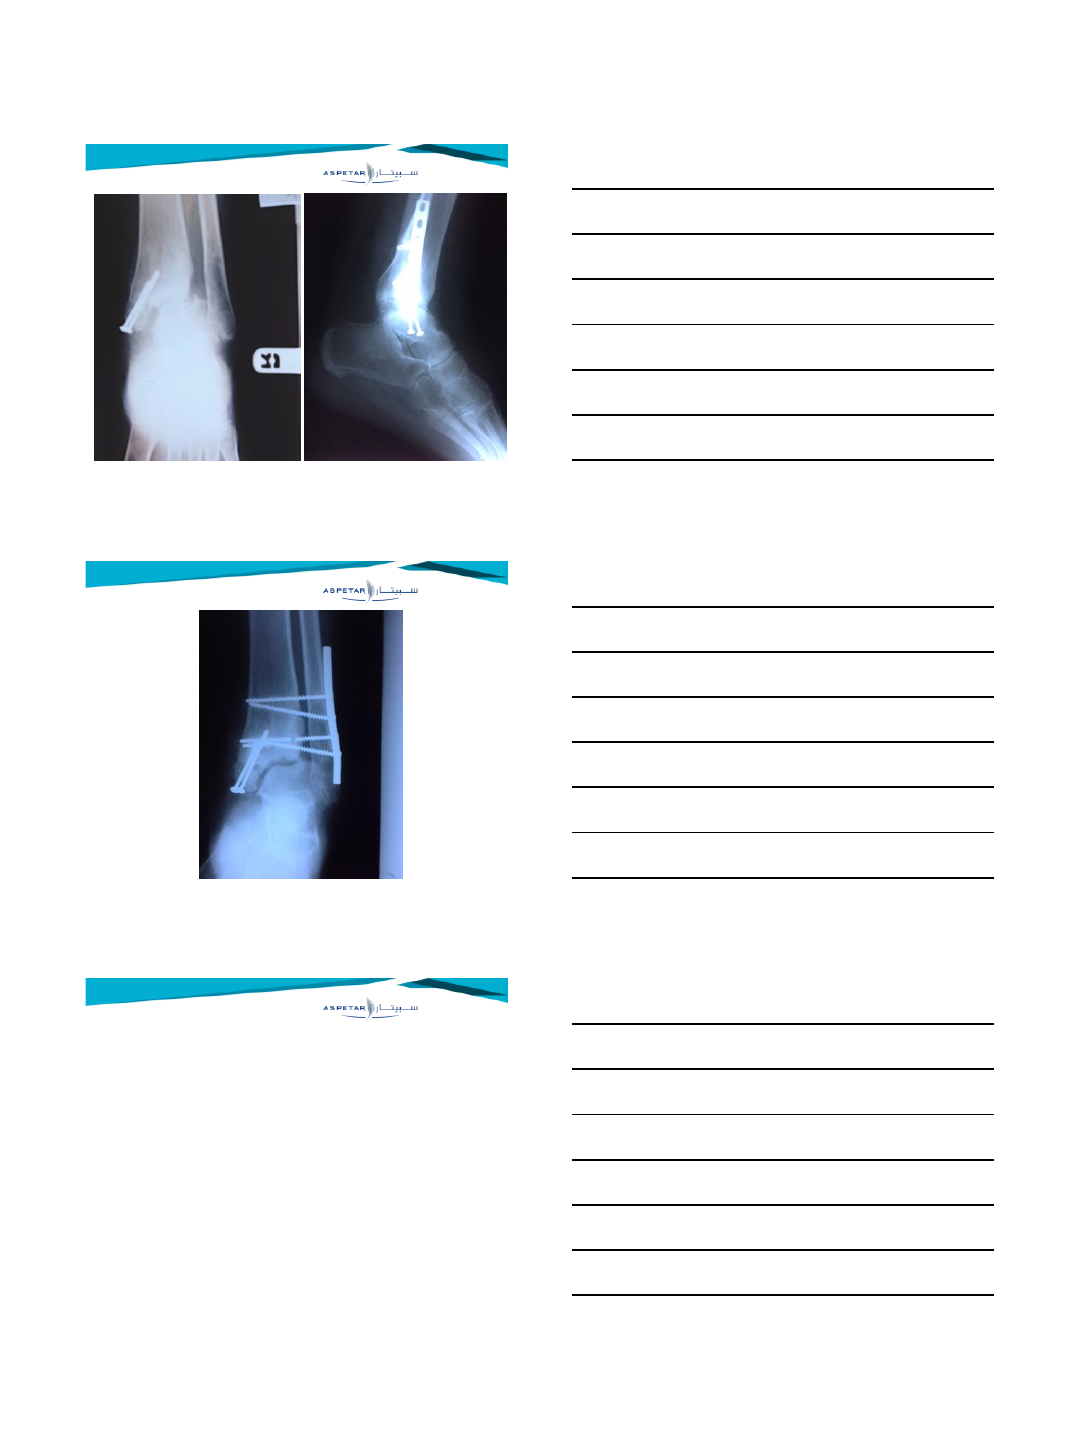

TREATMENT

•Untreated have poor prognosis

•No distinction between subacute and chronic

•Syndesmotic enhancement with lag screw or

positioning screw (3 or 4 cortices) or suture

button technique or combination

•Arthroscopic debridement with lag screw or

Late syndesmotic widening

•Treatment options for late syndesmotic widening

•Syndesmotic screw fixation

•Debridement (with screw fixation)

•Repair (with screw fixation)

•Reconstruction (with screw fixation)

•Bone block transfer (with screw fixation)

•Correction osteotomy

•Arthrodesis

Delayed operative treatment of syndesmotic instability. Current concepts review.

Van den Bekerom M, de Leeuw PAJ, van Dijk CN

Injury 2009

Van den Bekerom M, de Leeuw P, van Dijk CN

Syndesmotic screw stabilisation

•Late syndesmotic screw fixation was advocated by Key (1934)

and Mullins (1958)

•Opinion: only screw fixation for chronic instability is not

sufficient